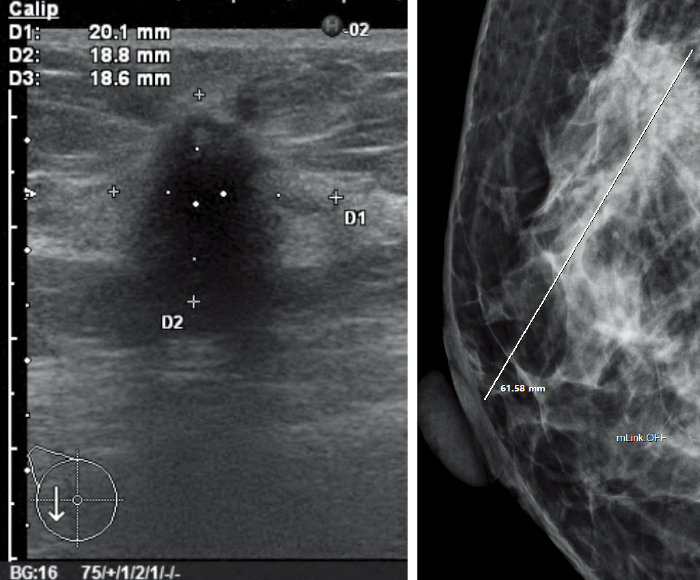

Los valores para la medición de ROI y rayos X pueden obtenerse a partir de la información de cada modalidad de imagen.

ROI (región de interés)

Curva de intensidad temporal

Escala